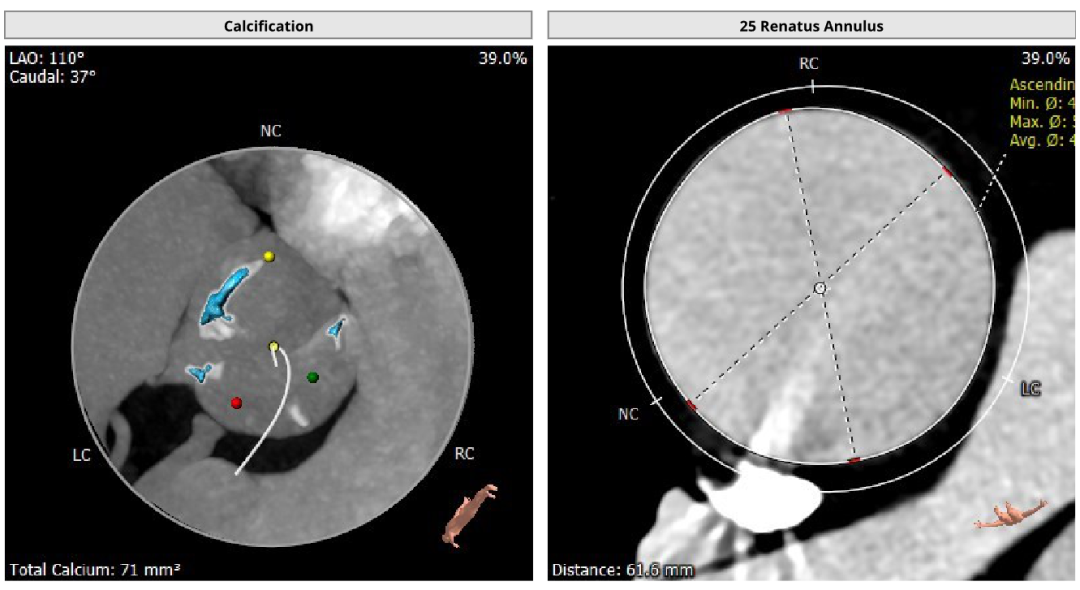

患者女性,73岁,Type 1二叶瓣,左-右融合。主动脉瓣重度狭窄,瓣环及瓣叶钙化,瓣环面积径24.9mm。左冠高度13.5mm,右冠高度16.8mm。外周入路可见明显钙化,内径尚可。

手术经心尖入路,术中植入25# RENATUS®球扩式经导管主动脉瓣。输送器顺利通过,瓣膜精准释放。瓣膜释放位置理想、形态及功能良好,术后无明显瓣中及瓣周反流等并发症。

术前评估